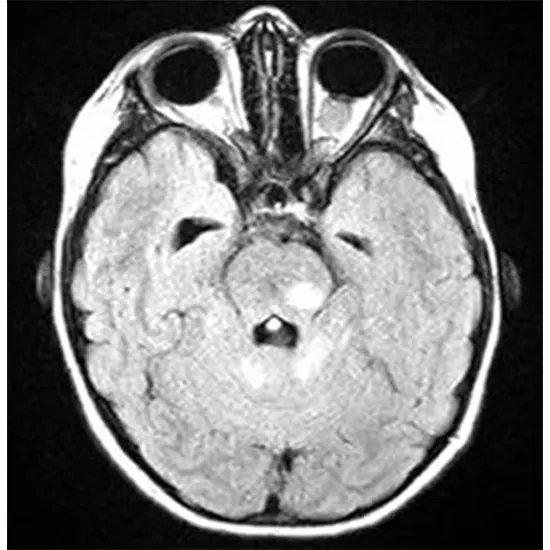

Optic nerve glioma, also known as optic pathway glioma, is a rare type of brain tumor that originates in the cells of the optic nerve or the optic pathway, which is the pathway that transmits visual information from the eyes to the brain. Optic nerve gliomas are most commonly diagnosed in children and adolescents, although they can also occur in adults.

Diagnosis of optic nerve glioma usually involves a thorough eye examination, including dilated fundus examination to visualize the optic disc, as well as imaging studies such as magnetic resonance imaging (MRI) or computed tomography (CT) scan to determine the location, size, and extent of the tumor. Biopsy may be needed to confirm the diagnosis and determine the specific type of glioma.